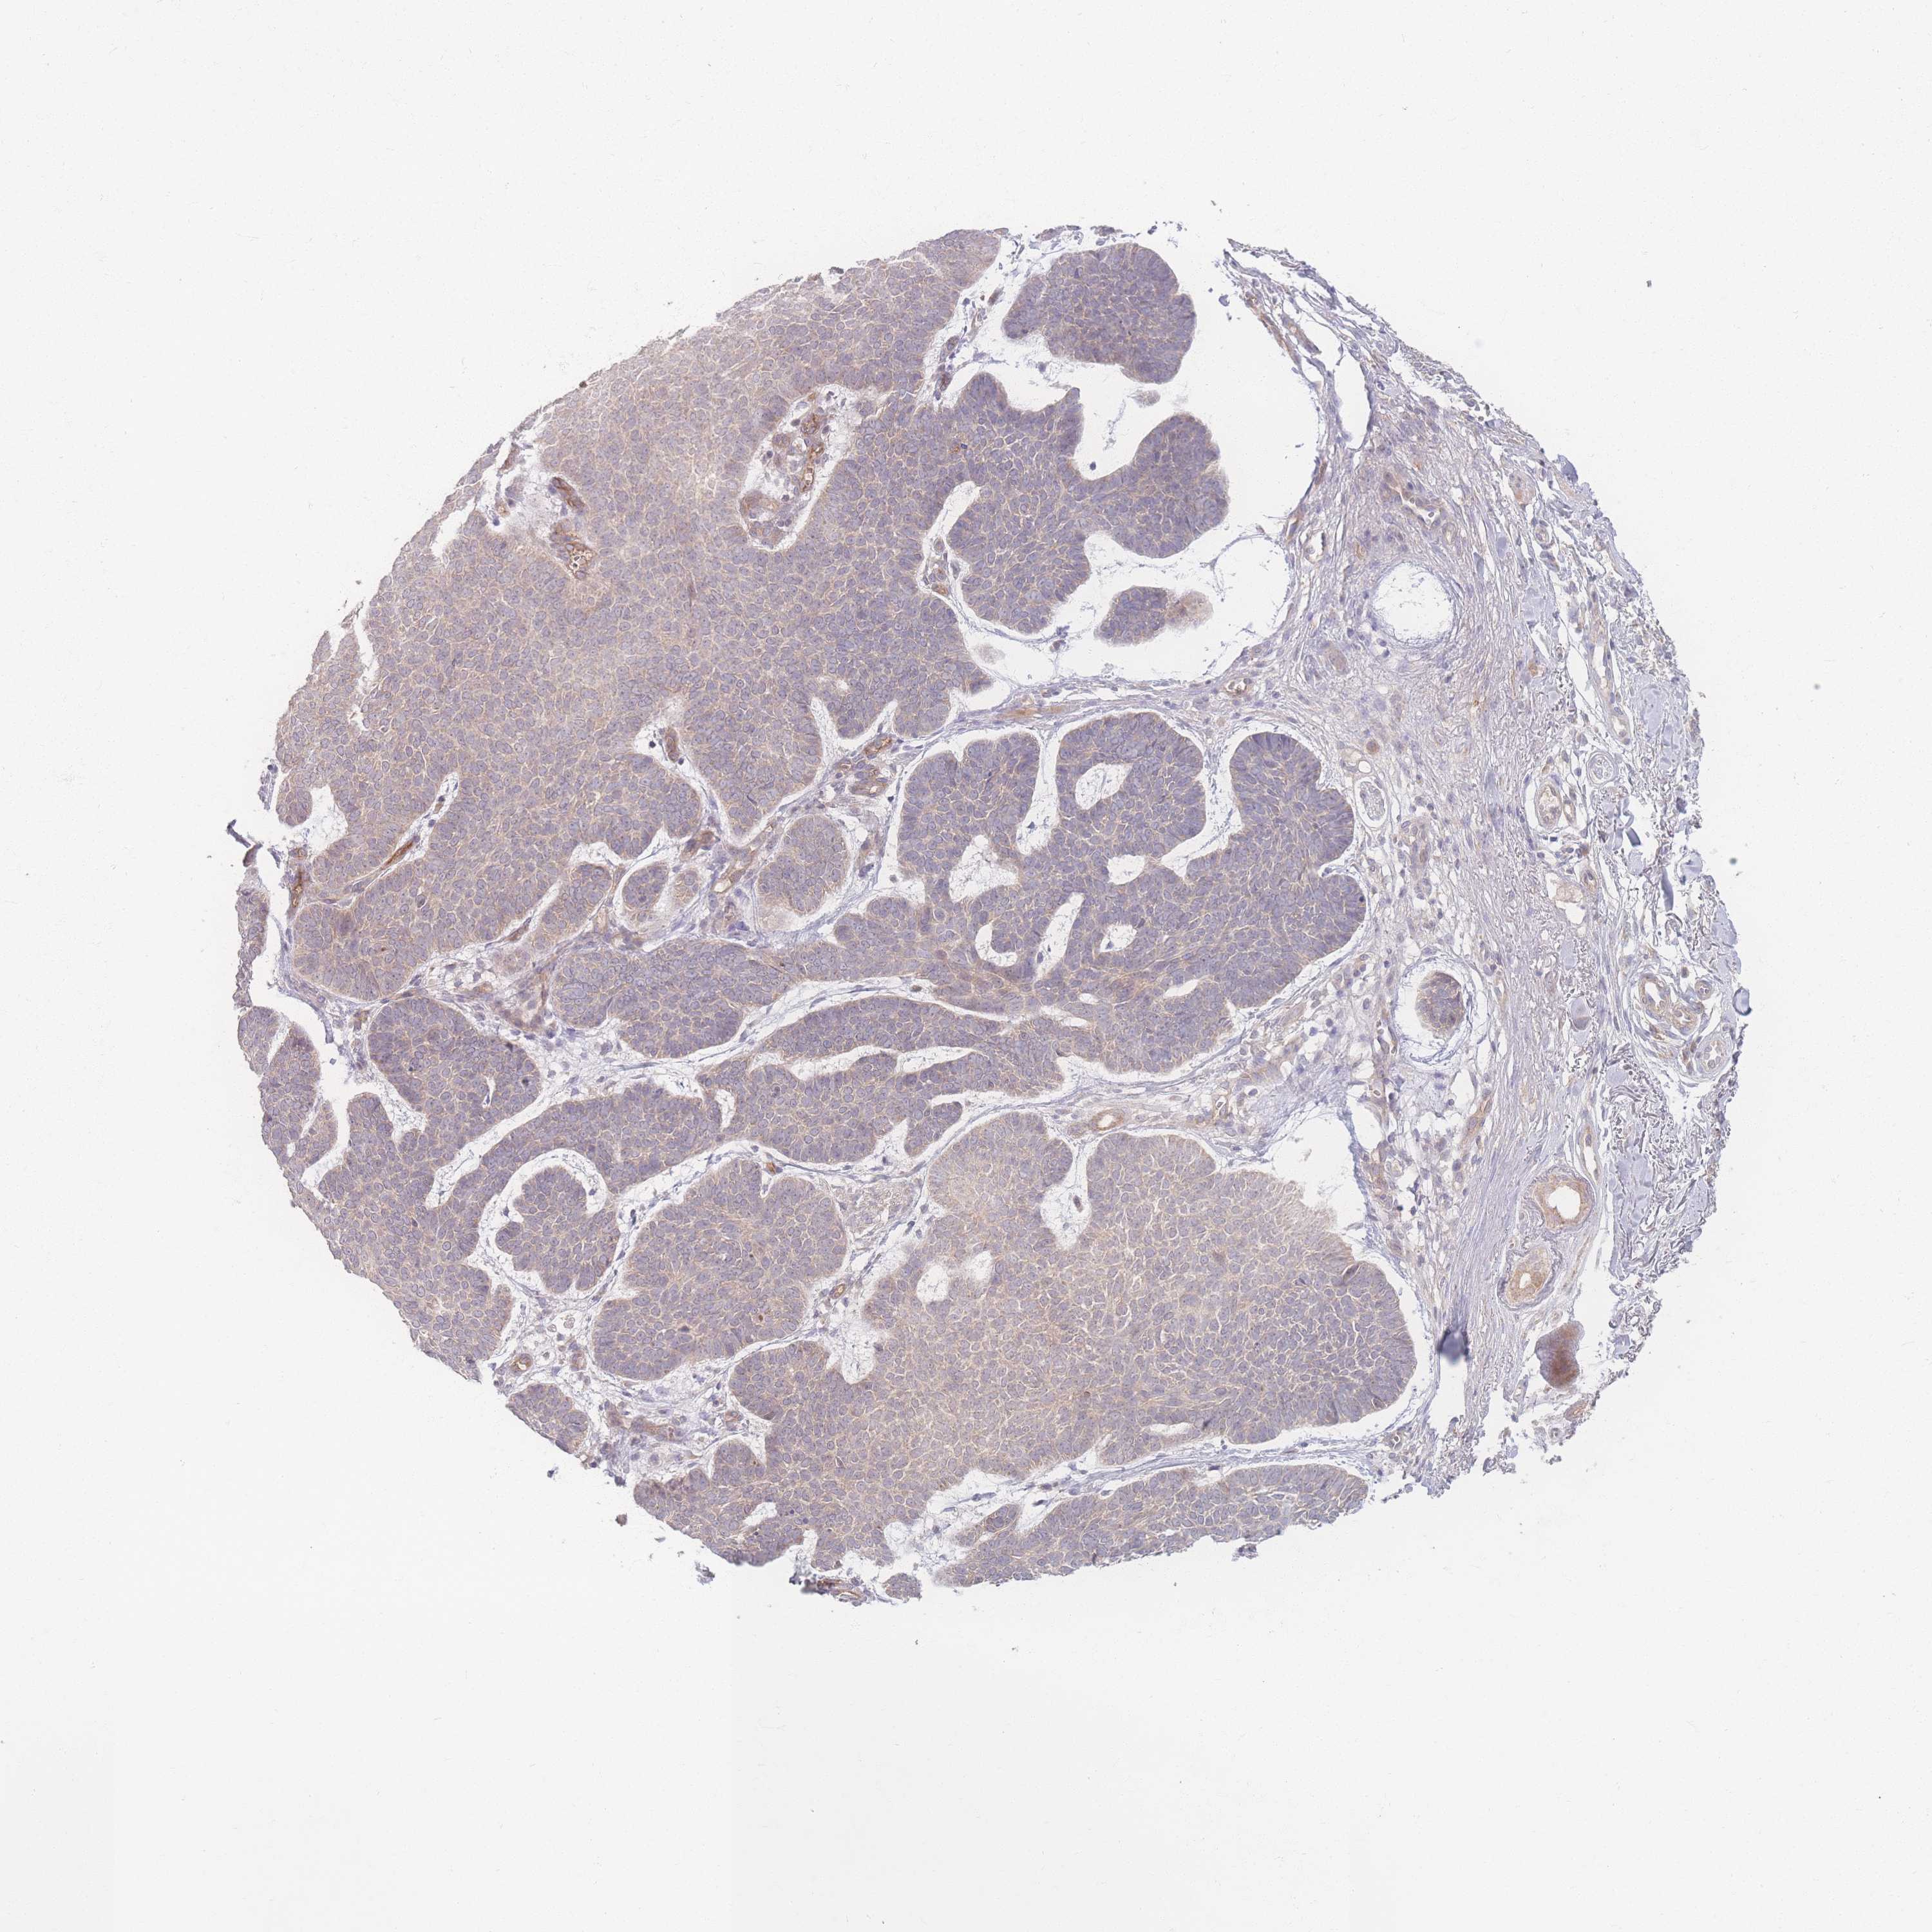

Basal cell and squamous cell cancer

SKIN CANCER - Protein expressioni

A mouse-over function shows sample information and annotation data. Click on an image to view it in a full screen mode. Samples can be filtered based on level of antibody staining by selecting one or several of the following categories: high, medium, low and not detected. The assay and annotation is described here.

Antibody stainingi

Antibody staining in the annotated cell types in the current human tissue is reported as not detected, low, medium, or high, based on conventional immunohistochemistry profiling in selected tissues. This score is based on the combination of the staining intensity and fraction of stained cells.

Each image is clickable and will lead to virtual microscopy that enables deeper exploration of all samples and also displays staining intensity scores, fraction scores and subcellular localization as well as patient and tissue information for each sample.

Antibody HPA036302

Staining

High

Medium

Low

Not detected

Intensity

Strong

Moderate

Weak

Negative

Quantity

>75%

75%-25%

<25%

None

Location

Nuclear

Cytoplasmic/membranous

Cytoplasmic/membranous,nuclear

Squamous cell carcinoma, metastatic, NOS